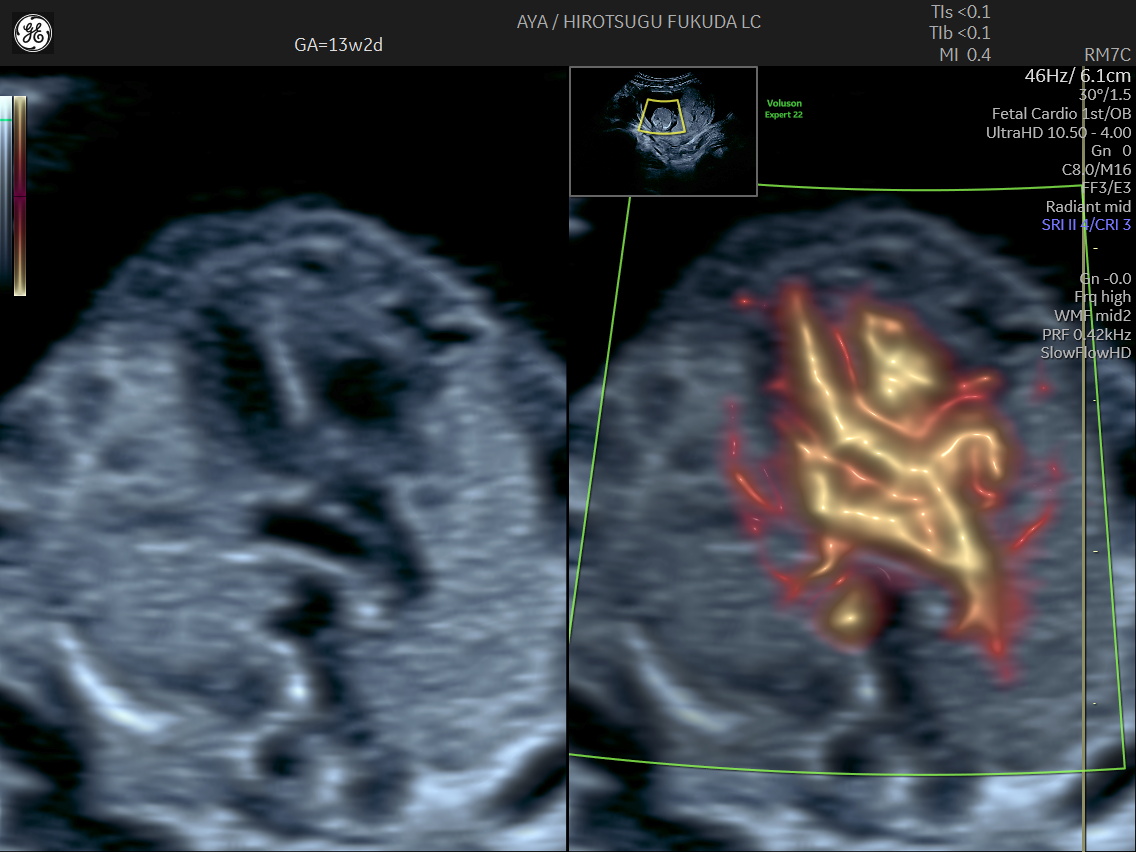

胎児心臓の初期評価

妊娠初期では観察が難しい胎児心臓についても、SlowflowHDを用いた血流描出を併用し、可能な範囲で流出路や大血管の位置関係の評価を行っています。

初期心臓評価の実際

下記は、妊娠初期における血流描出の一例です。初期心臓評価に関する取り組みについては、国際学術誌 Journal of Ultrasound in Medicine にも報告しています。

妊娠13週のslowflowHDによる心臓

妊娠13週の心疾患症例